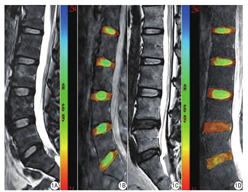

代表性腰椎矢状位T2WI图像及相应的T1rho后处理伪彩图像见图1。

38例下腰痛者及28名无症状志愿者共330个腰椎间盘纳入本研究,其各节段腰椎间盘(L1/2、L2/3、L3/4、L4/5、L5/S1)NP区T1rho值见表2。下腰痛者L1-S1各节段椎间盘NP区T1rho值均比对照组低,且差异存在统计学意义(P<0.01),且下腰痛者L4/5、L5/S1椎间盘T1rho值明显低于L1/2、L2/3(P<0.05)。